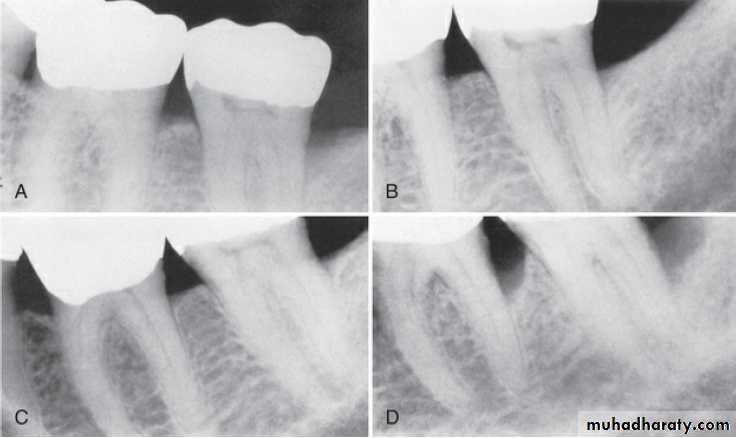

One likely explanation for the recurrence of periodontal disease is incomplete subgingival plaque/biofilm and calculus removal

The regrowth of subgingival biofilm is a slow process compared with that of supragingival biofilm. During this period (perhaps months), the subgingival biofilm may not induce inflammatory reactions that can be appear at the gingival margin.

Thus inadequate subgingival biofilm control can lead to continued loss of attachment, even without the presence of clinical gingival inflammation.

Scaling and root planing are generally not effective at sites with probing depths of 6 mm or greater.

Radiographic examination must be individualized, depending on the initial severity of the case and the findings during the recall visit. These are compared with findings on previous radiographs to check the bone height and look for repair of osseous defects, signs of trauma from occlusion, periapical pathologic changes, and caries.